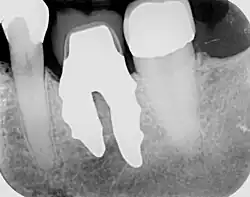

Röntgenaufnahme eines wurzelanalogen Zahnimplantats mit Einzelwurzel im rechten unteren zweiten Prämolaren